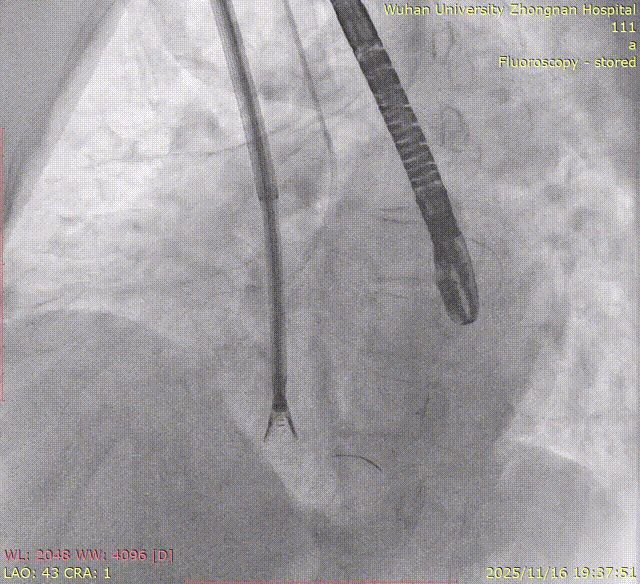

The entire procedure was guided by both Transesophageal Echocardiography (TEE) and Digital Subtraction Angiography (DSA).

Left Atrial Appendage Closure (LAAC):The delivery system was successfully advanced into the left atrium. Precise measurements of the LAA orifice and depth were taken under multi-angle TEE and DSA guidance. Given the LAA's large orifice (nearly 34mm), conical cauliflower shape, and shallow usable depth, a LACBES2434 occluder was selected. Using the "extreme coin technique," the closure was successfully achieved.

DSA

K-Clip® Tricuspid Annuloplasty (Seamless Transition):Immediately after LAAC, the operators established a new vascular access route and advanced the K-Clip® delivery system directly into the right atrium, targeting the posterior-septal and anterior-posterior commissures of the tricuspid annulus. Under real-time ultrasound guidance, the team precisely anchored, clipped, and released the devices.

5.Right coronary angiography confirming no impact on the RCA after clipping.

8.Right coronary angiography confirming no impact on the RCA before releasing the second implant.